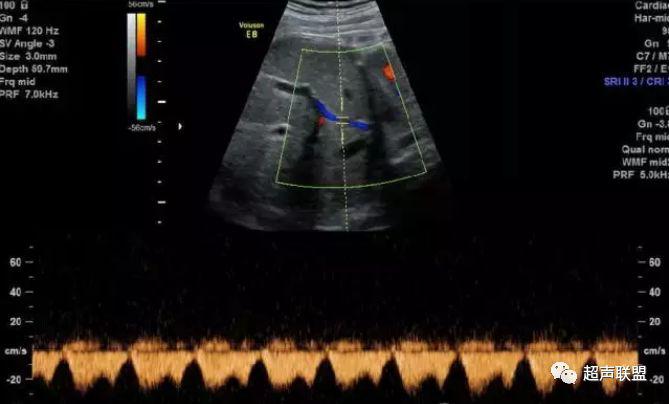

1 胎儿脐动脉测定

缺氧首先出现的变化是舒张末期血流降低,S/D值、RI值和PI值升高。当缺氧进入再分配晚期时,可逐渐出现舒张期血流减少、舒张期血流缺失。失代偿期出现脐动脉血液逆流,舒张期血流倒置。

2、脐动脉标准:孕30周后,S/D>3;晚孕期,RI >0.75;孕18~20周后,脐动脉舒张期缺如或反向(后者见于严重的宫内缺氧者);

图1 正常脐动脉血流频谱

图2 脐动脉舒张期血流消失或反向